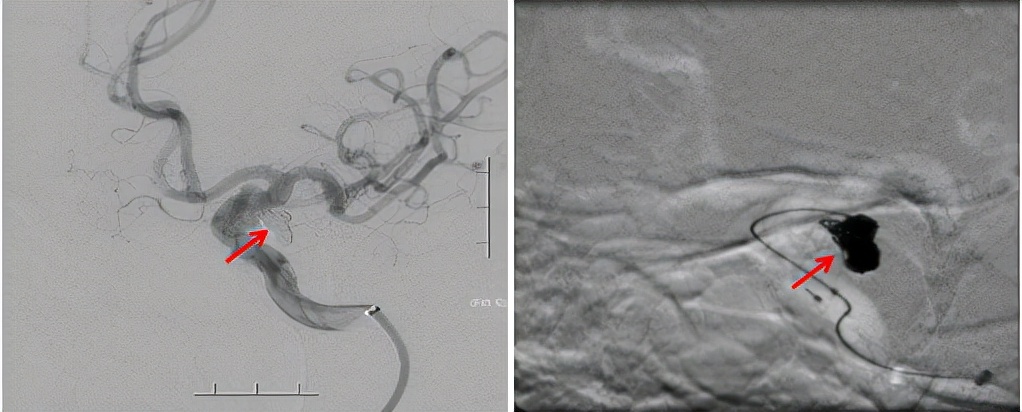

完善术前相关检查,未见明显手术禁忌症,最终神经外三科团队在全麻下为患者实施脑血管造影术及脑动脉瘤栓塞术。